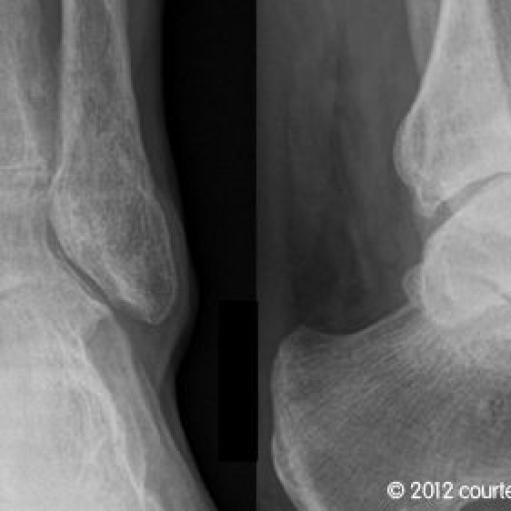

Obere Sprunggelenksendoprothese

Seit 2003 werden in unserer orthopädischen Abteilung in geeigneten Fällen die arthrotisch oder unfallbedingt zerstörten Sprunggelenke durch ein „künstliches Sprunggelenk“ ersetzt.

Wir verwenden dabei die von Prof. Hintermann entwickelte HINTEGRA-Totalendoprothese ,die zementfrei mit nur geringer Knochenresektion eingebaut wird.

Der Vorteil gegenüber der Arthrodese (Versteifung) ist evident: die Beweglichkeit im oberen Sprunggelenk bleibt erhalten oder wird teilweise wiedergewonnen, die bei der Versteifung gefürchtete Arthrose der benachbarten Gelenke wird vermieden. Die überwiegende Zahl der von uns behandelten Patienten ist bisher hoch zufrieden.